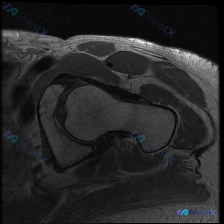

看到一份肩部MRI轴位T1序列图像,原始问题是‘观察到的病理是什么’,有人第一反应是盂唇病变,但影像分析报告里有几个细节: 1. 肩胛下肌肌腱连续性中断,有回缩 2. 肱二头肌长头腱在结节间沟内结构模糊 3. 关节盂唇前下部未见明显Bankart样裂隙 大家第一反应会往哪个方向靠?觉得最核心的病理是...

看到一份肩关节MRI单T1序列的病例资料,先放上来讨论: 患者资料(影像相关): - 扫描序列:肩关节轴位T1加权图像 - 主要发现: 1. 肩胛下肌腱附着处信号略有不均,前方间隙软组织信号紊乱 2. 盂唇形态尚完整,但T1序列对病变评估有局限 3. 未见典型Hill-Sachs损伤、肩峰下撞击征象...